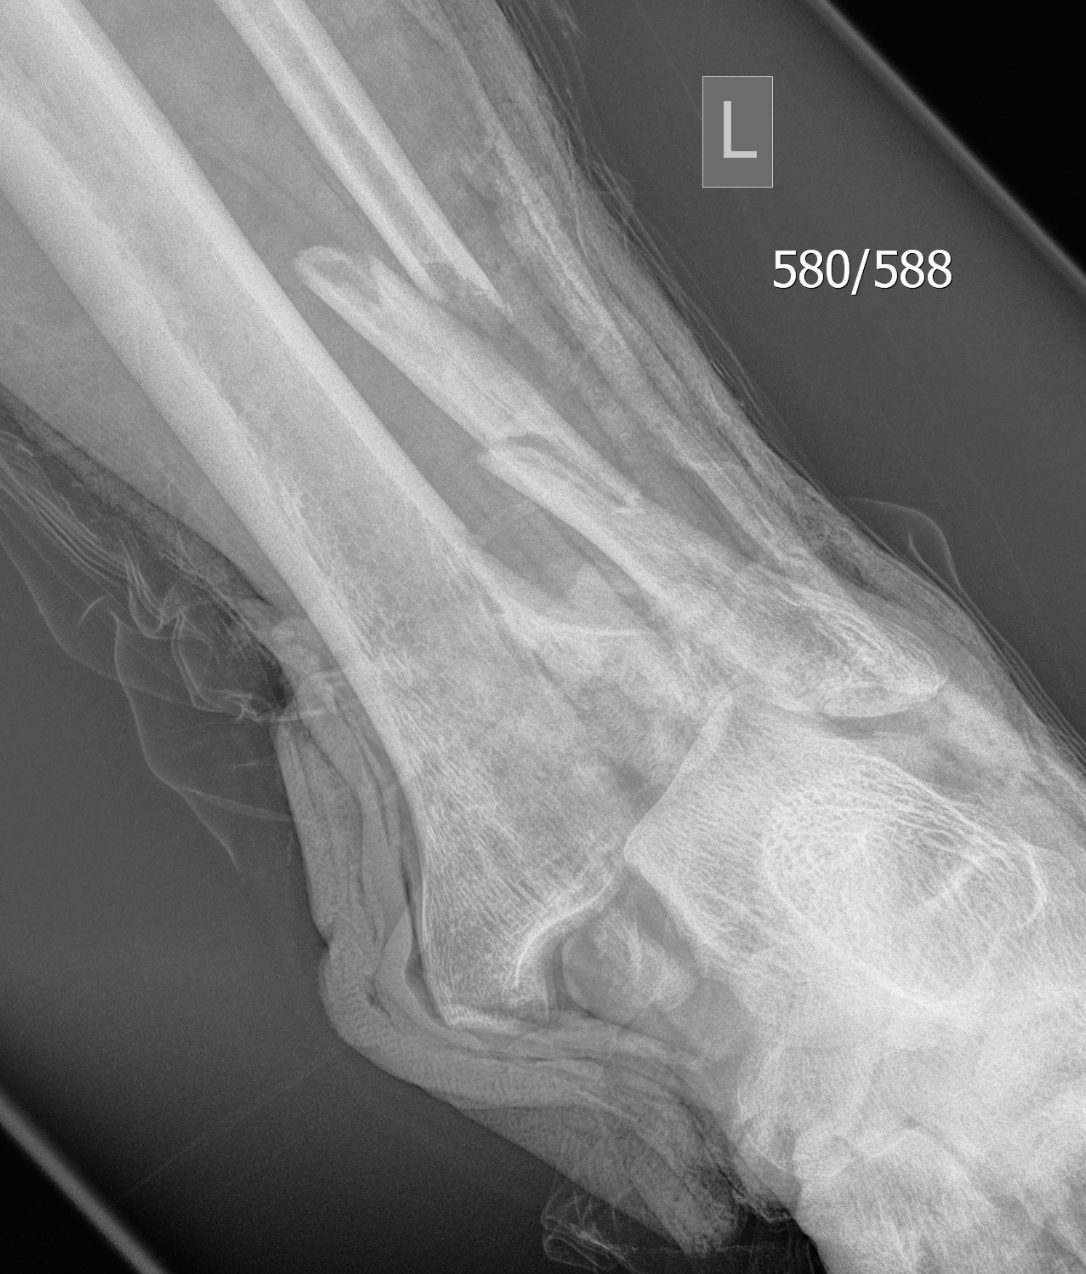

CT scan

Commonly 3 fracture configurations

- medial malleolus

- posterolateral fragment / Volkmann

- anterolateral fragment / Chaput

CT after external fixation application